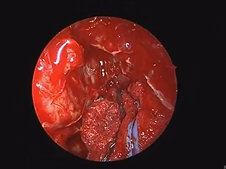

Transcervical Exploration of Parapharynx for Deep Lobe Parotid Pleomorphic Adenoma

- Date : 01/01/2020

Uvulopalatopharyngoplasty (UPPP)- Lateral Expansion Pharyngoplasty Variant with Uvulopalatal Flap